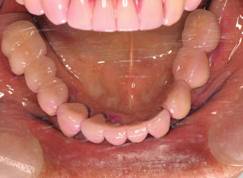

上顎

下顎

術後。上部構造はハイブリッドレジンです。しっかり嚙めるようになり喜んでいただきました。

上部構造装着後6年。ハイブリッドレジンを使用したため、少し艶がなくなってきました。上部構造の材料には金属、ハイブリッドレジン、セラミックなどがあります。セラミックはきれいですが欠けやすいため、最近はフルジルコニアを使っています。

上顎 少しすり減ってきました。

下顎。12か月に一度メインテナンスをしています。